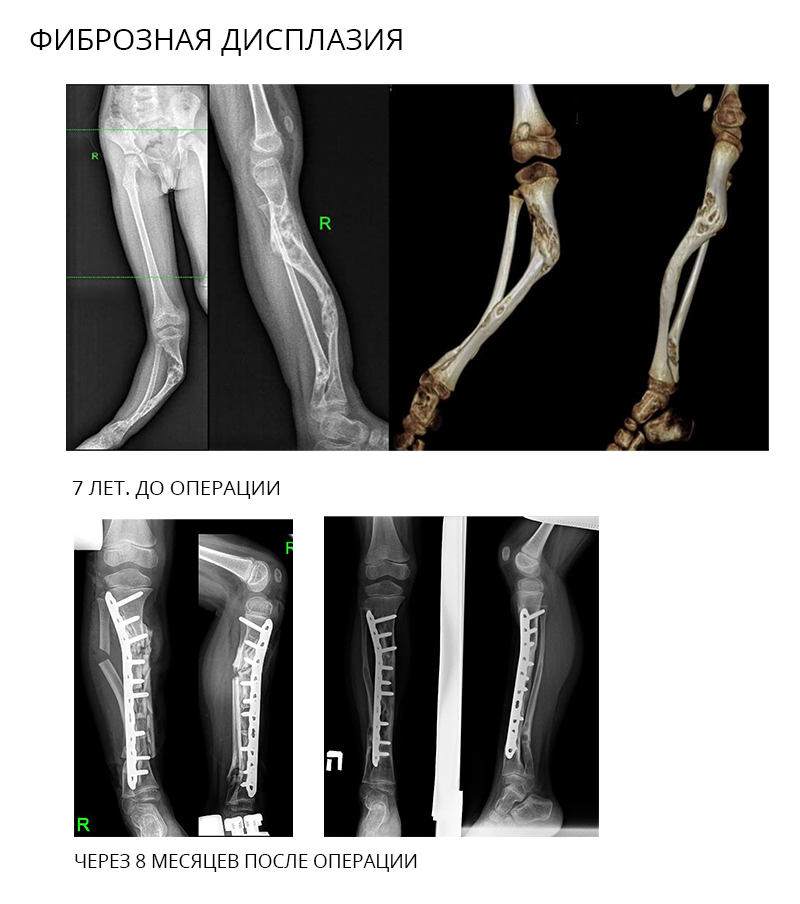

Корригирующие остеотомии

Остеотомия или пересечение кости - одна из самых распространенных операций в ортопедии. Цель ее – устранить деформацию (искривление) кости. В качестве фиксирующего устройств могут быть использованы пластины (накостный остеосинтез), интрамедуллярные стержни с блокированием (внутрикостный остеосинтез) и аппарат Илизарова.

Корригирующая остеотомия - это хирургическая операция, благодаря которой устраняется деформация кости или сустава, выполняемая путем совершения искусственного перелома. С помощью этой процедуры можно улучшить состояние тазобедренного, голеностопного и коленного суставов. Все остеотомические операции, проводимые нашими специалистами, направлены на восстановление нормального положения ног человека при ходьбе.

Примеры применения интрамедуллярного остеосинтеза